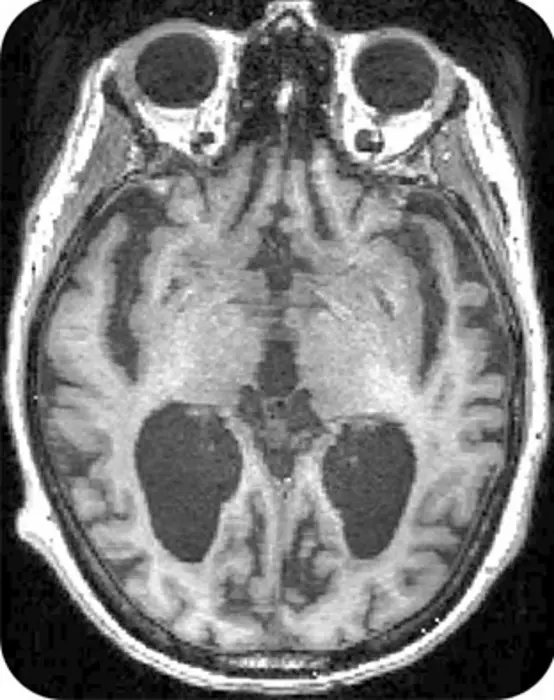

This MRI scan shows a brain with Alzheimer's disease

In the brain on the left the disease is in a stable state, while in the brain on the right the disease is Slowly Progressive. The AI model developed by the team can tell these apart precisely.